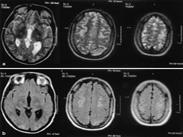

賓斯旺格病

• 賓斯旺格病

628健康網為您分享有關賓斯旺格病的癥狀,賓斯旺格病的治療方法,賓斯旺格病的預防知識,賓斯旺格病的癥狀圖片,賓斯旺格病...